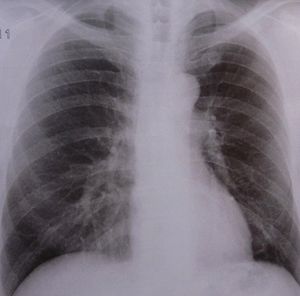

Sie sind hier: Startseite Nachrichten Gesundheit TBC: Vitamin D statt immer neuer Antibiotika Lunge: Millionen Menschen sterben an TBC.

Lunge: Millionen Menschen sterben an TBC.

Bild: pixelio.de, Dieter Schütz